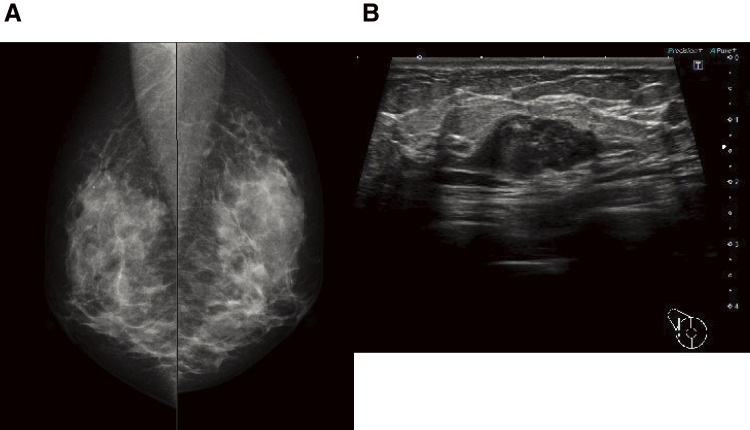

Case presentation: We describe the case of a 44-year-old female patient with invasive ductal carcinoma of the right breast. Cobblestone papillomatosis was present in the gingiva. She had a medical history of bilateral adenomatous goiters for 10 years. Her mother had been diagnosed with breast cancer, thyroid and tongue tumors, gastric polyps, hepatic hemangioma, and collagen disease. Additionally, the patient's maternal grandmother had a history of colon cancer. Based on the patient's family history and physical findings, CS was suspected, and direct DNA sequencing analysis revealed a haplotype c.634del mutation in exon 7 of the PTEN gene. Although there is no clear evidence supporting risk-reducing surgery for PHTS, a right nipple-sparing mastectomy, sentinel lymph node biopsy, and tissue expander reconstruction were performed.